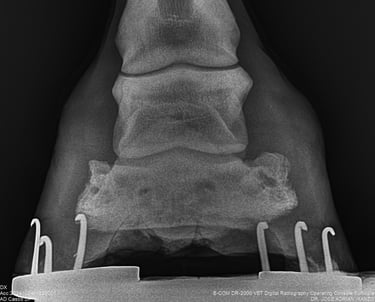

DIAGNOSTICO POR IMAGENES: ECOGRAFIA Y RADIOGRAFIA